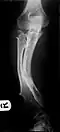

Multiple osteochondromas causing deformity of the forearm (shortening of the radius with secondary bowing of the ulna) -